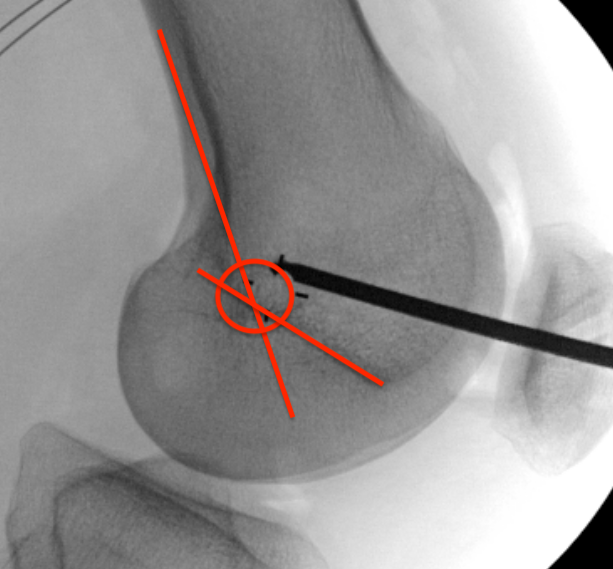

Femoral attachment

- 4 mm proximal and posterior to medial epicondyle

- image intensifier: intersection of the posterior femoral condyle with Blumensaat's line

- 40o anterior to avoid notch

- 40o proximal to avoid PCL tunnel